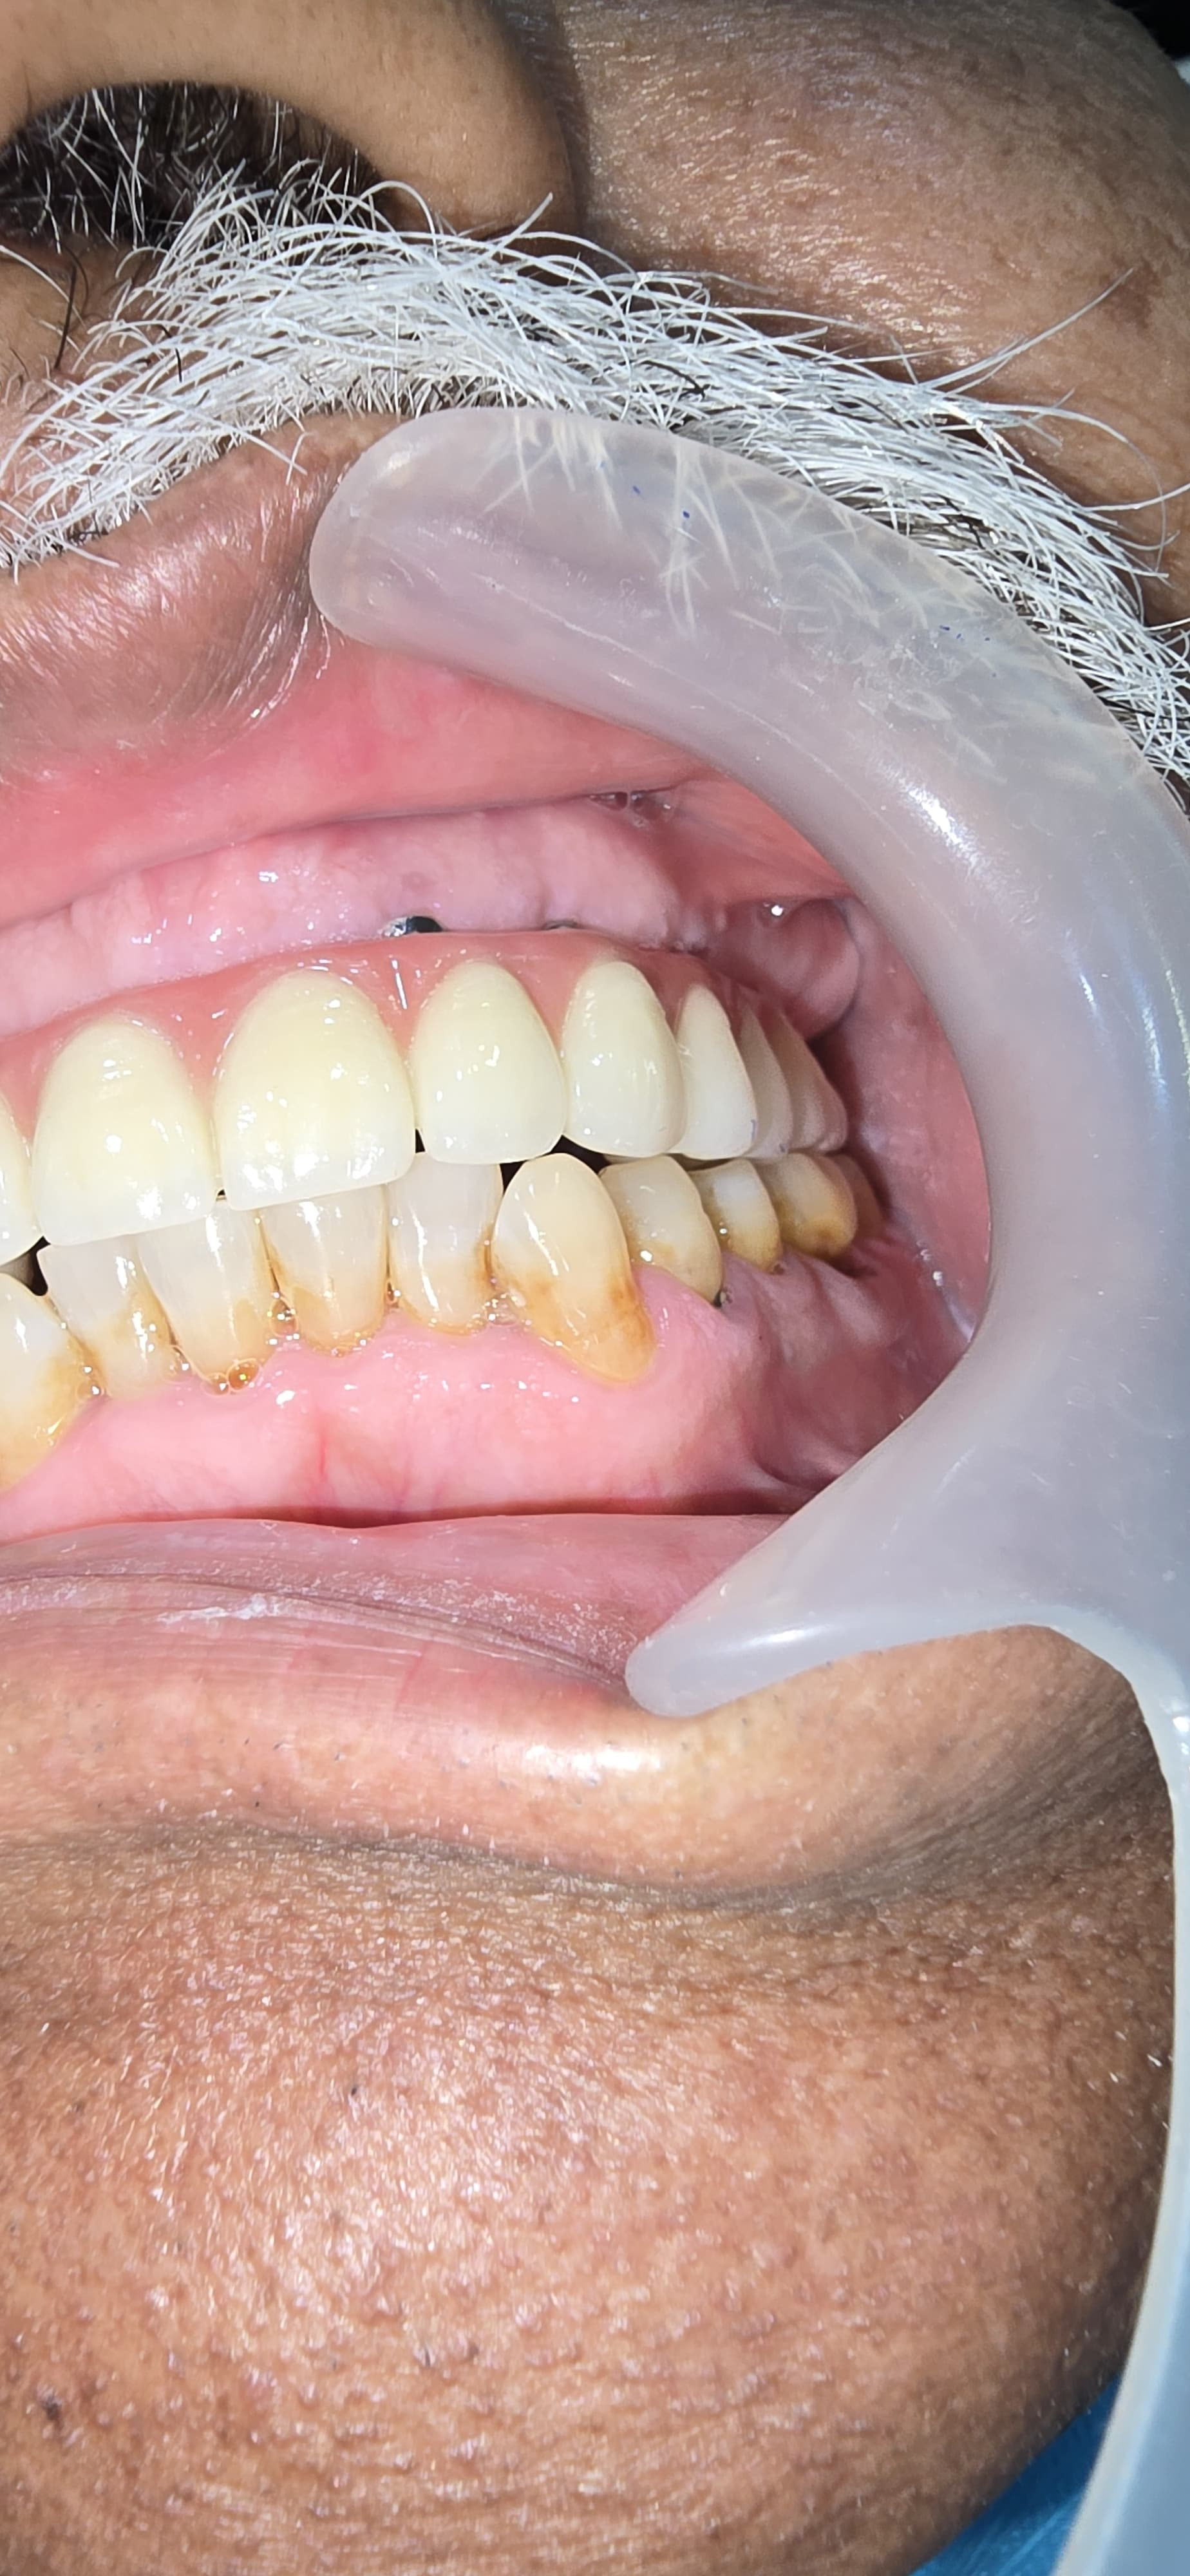

Full Mouth Implants with all Ceramic Crowns